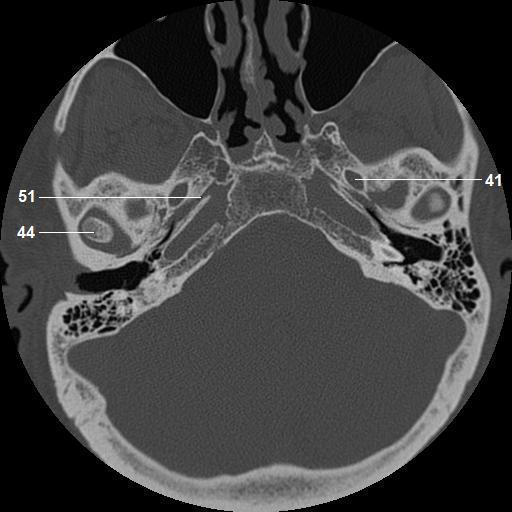

41. foramen ovale

44. head, mandibular condyle

51. petrosphenoidal fissure